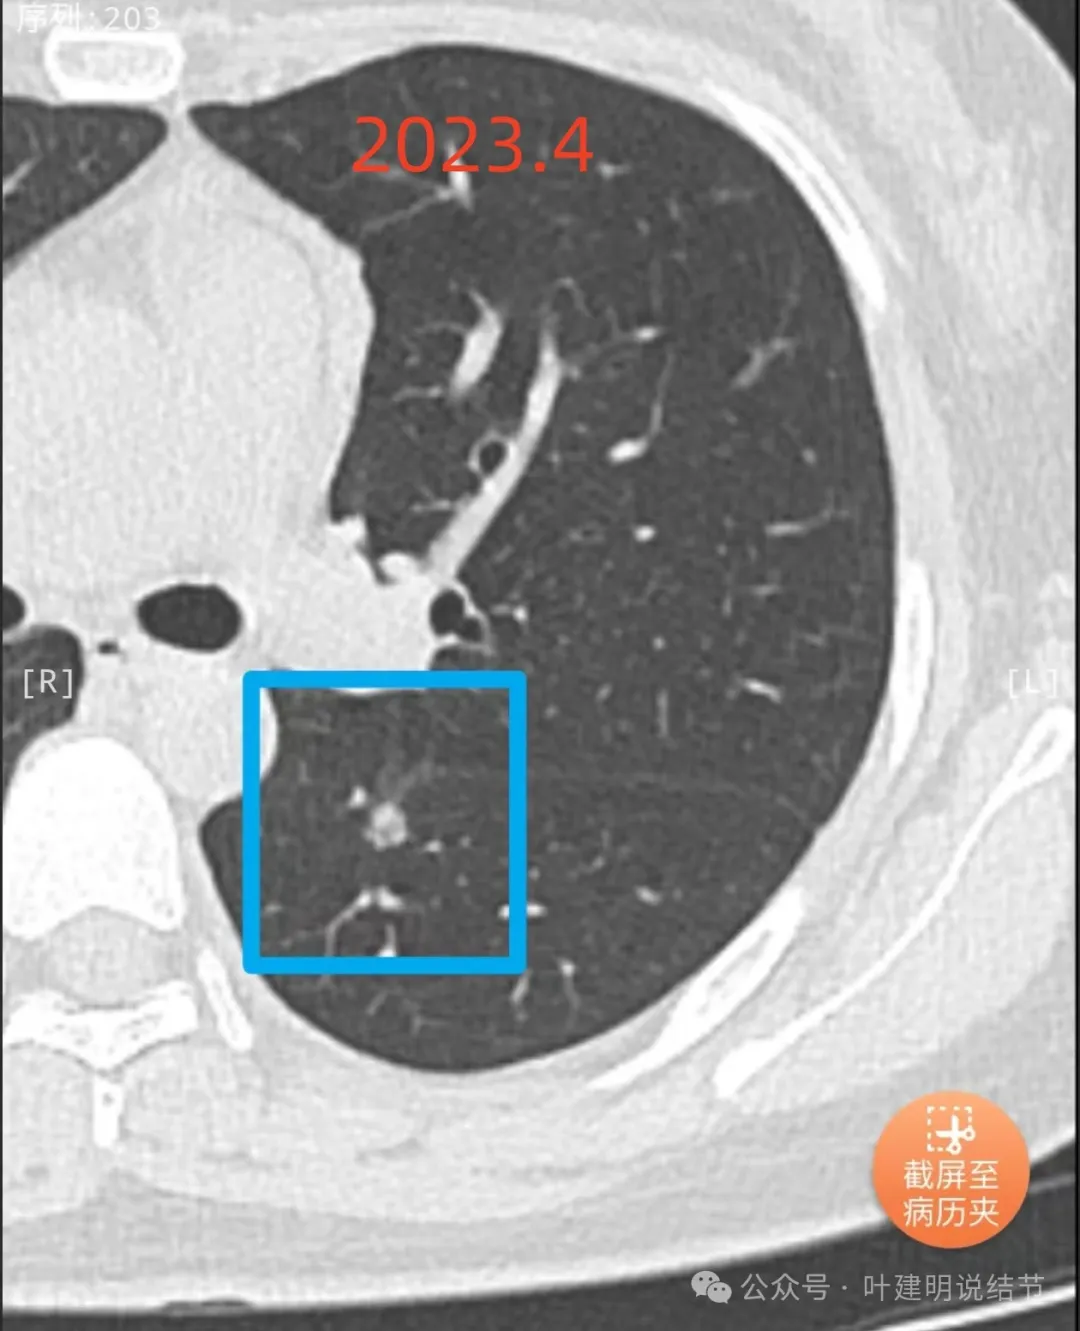

先看不同时间段最明显层面的影像:

2023年1月首次发现时即是混合密度,大部分是实性的,中间部分密度稍低像磨玻璃,离叶裂较近,整体轮廓较清,表面欠平整。

2023年4月复查没有显著变化,但表面是不平的,密度也是显得杂乱的。